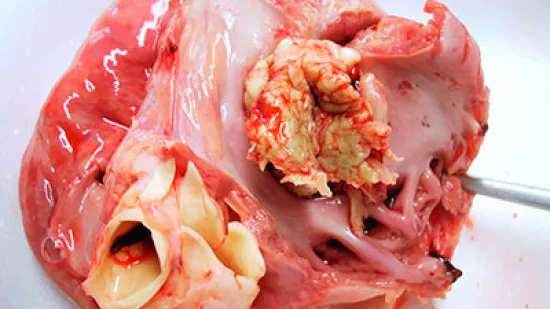

Semaine du 21-Fév-2022

Quelle est cette lésion sur une truie reproductrice qui vient de mourir ?